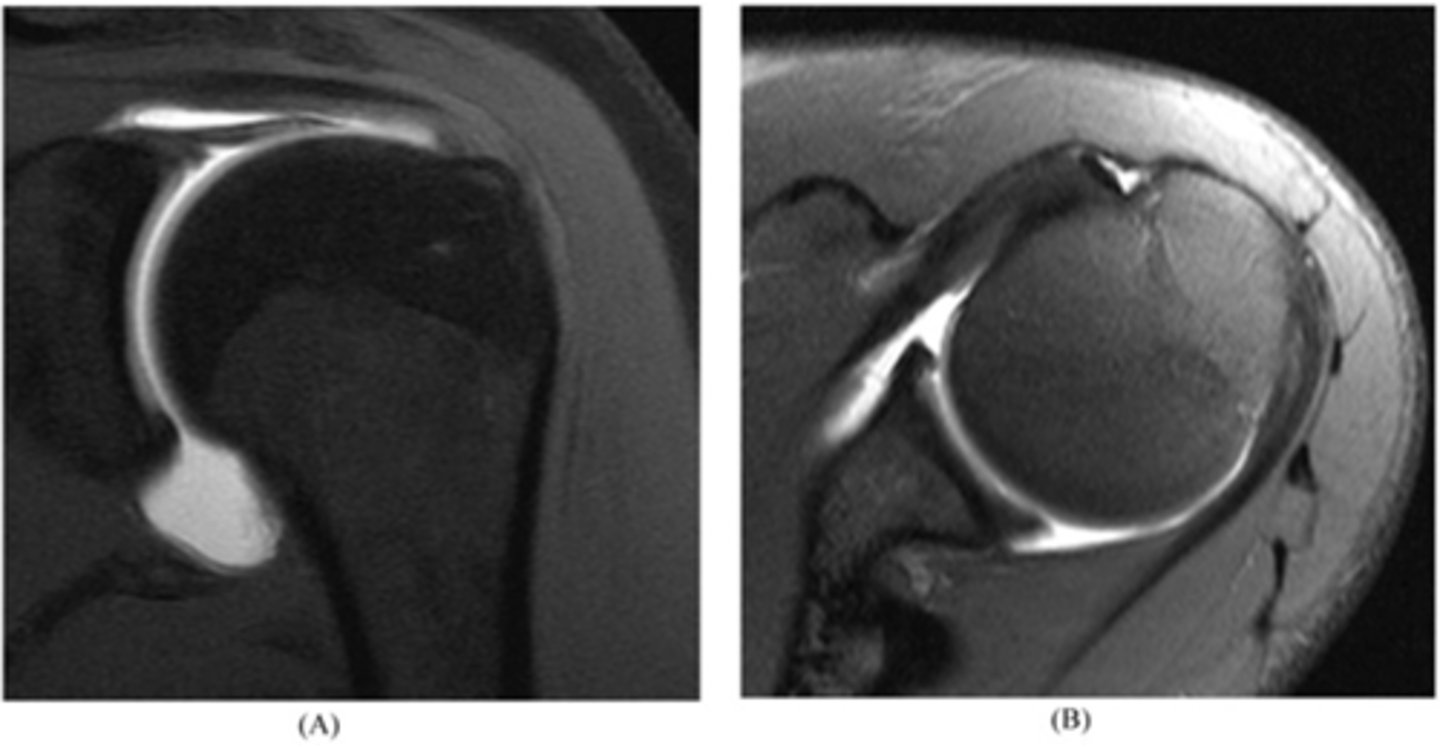

Left image: bursal-sided tear w/ SOME fibers still intact

RIght image: bursal sided AND intrasubstance tears

NOTE: our concern is these partial tears will progress to full tears

What are these images depicting w/ the rotator cuff? What is our concern?